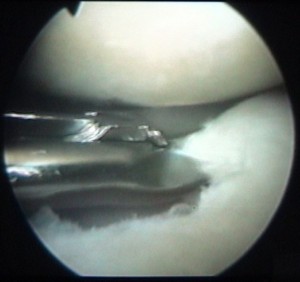

on voit la tête de la vis au milieu de la clé plate |

et le corps de la vis en-dessous |

cette vis sert à attacher le ligament |

et elle est maintenant vissée à fond |